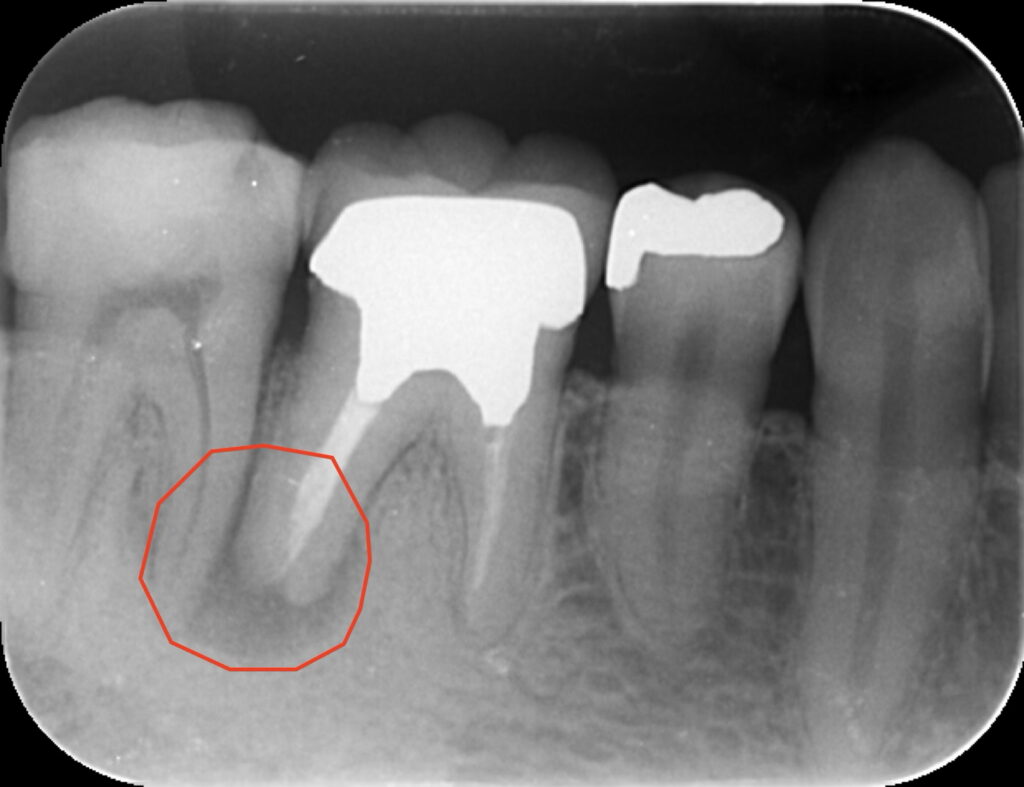

初診時の状況:

前医で「骨が溶けているので抜歯しかない」と診断されたケースです。根の先には大きな黒い影(透過像)が確認できます。確かに根尖病変は比較的大きいですが歯質が残っている今回の症例は「長持ち(Longevity)させられる」と当院では判断しました。